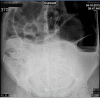

Sigmoid volvulus is a rare, but serious, complication that can occur during pregnancy. We present a case of a 33-year-old pregnant female in the third trimester with a sigmoid volvulus. Detorsion of the volvulus was performed during colonoscopy. The patient underwent an elective sigmoidectomy at a later date. Prompt diagnosis of the volvulus sigmoid is critical to minimize fetal and maternal morbidity and mortality. Sigmoidoscopic detorsion or surgical resection are the treatment options, depending on bowel viability. A review of the literature was done.